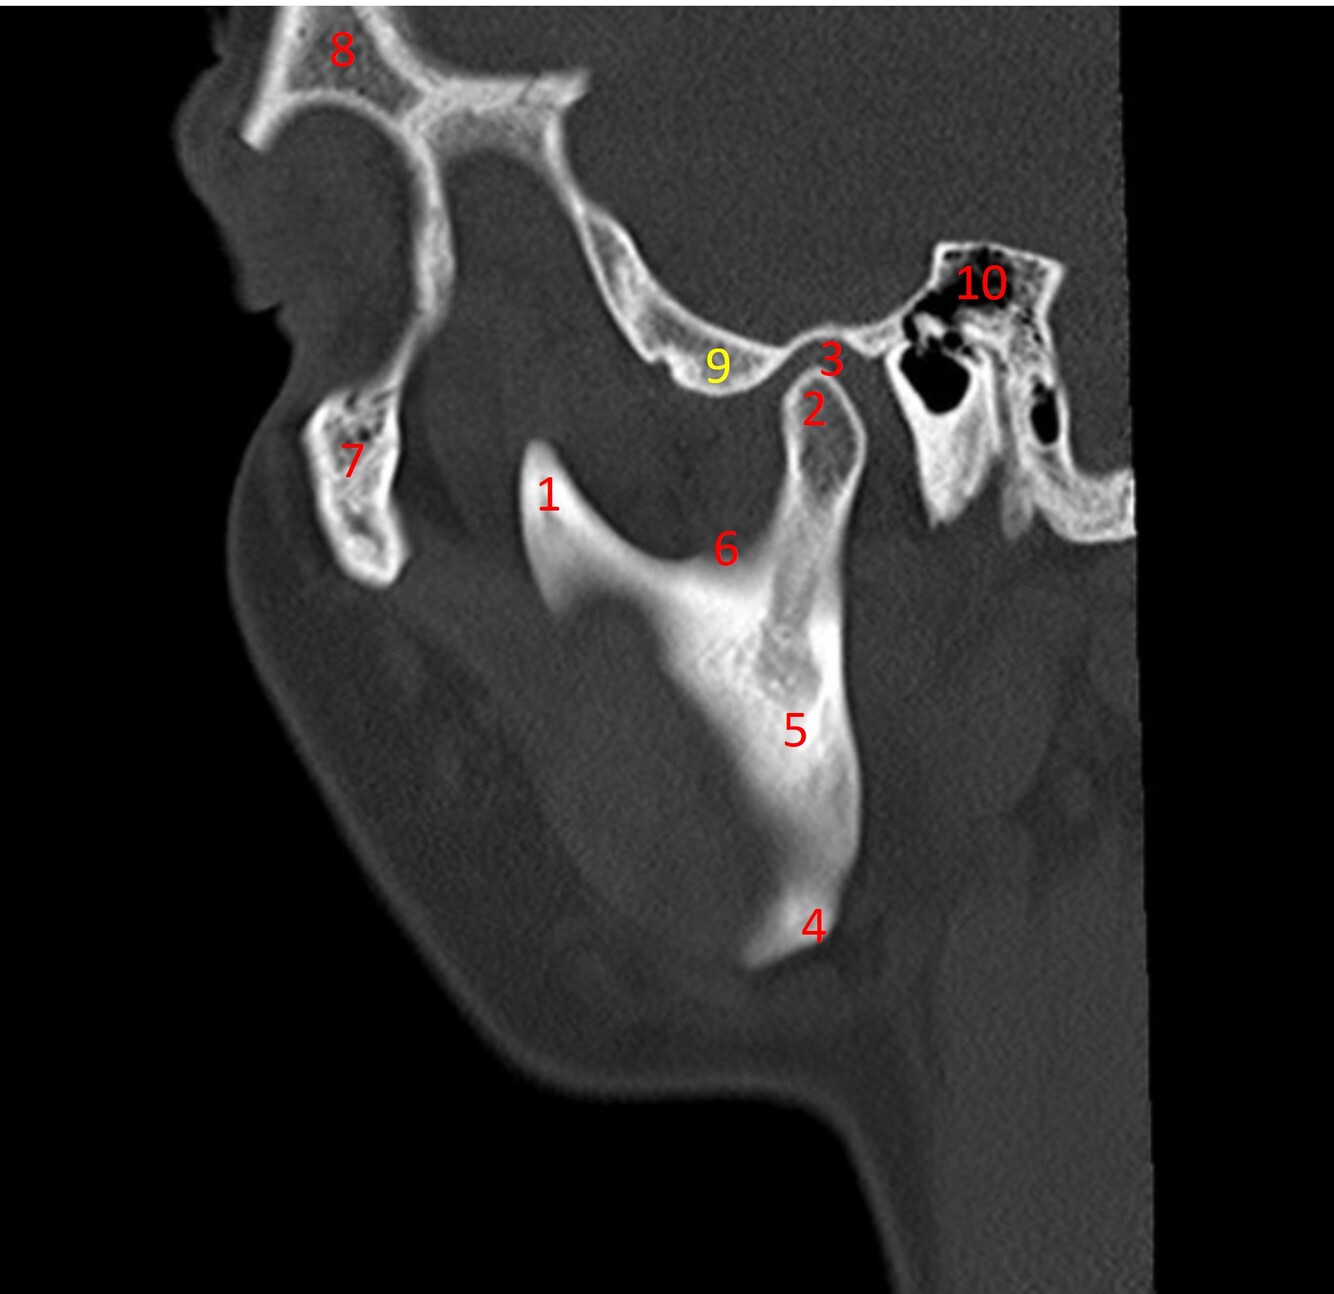

4

Label 1-10

A

1=Coronoid process of mandible

2=Mandibular condyle/condyloid process of mandible

3=Temporomandibular joint/mandibular fossa

4=Angle of mandible/Gonion

5-Ramus of mandible

6=Mandibular notch

7=Zygoma

8-Frontal bone

9=Articular eminence (Temporal bone)

10=Mastoid antrum